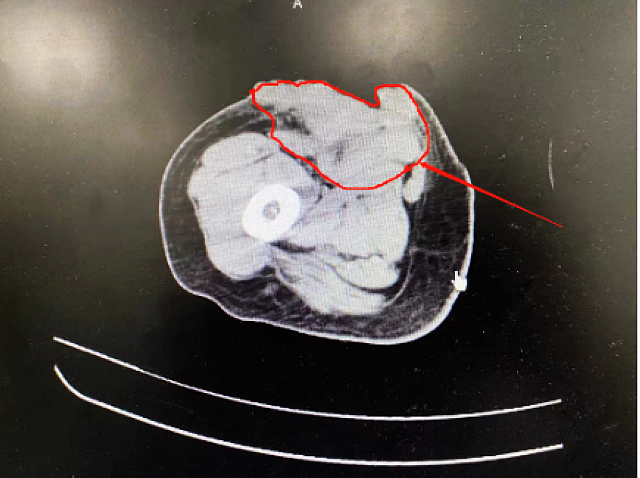

治疗后

经过5个周期的治疗,奇迹出现了:唐阿姨的颅内肿瘤、右侧大腿皮下肿瘤大小均较之前有明显缩小,也没有了头晕、头痛等症状,生活能自理,病情明显好转。